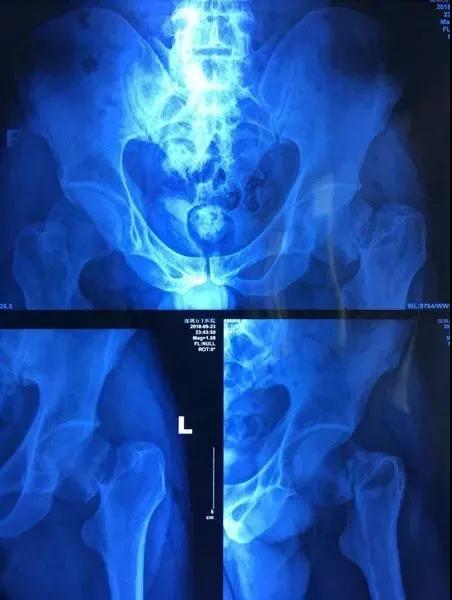

凌晨12点多,经拍片检查,贾先生被诊断为股骨颈骨折(头下型)。因骨折部位靠近股骨头,如果采取保守治疗或者骨折内固定,可能导致骨不愈合,股骨头缺血坏死,导致患者下肢疼痛,不能正常行走。谁愿意让后半生耽搁在轮椅上?

▲病患部位术前DR照